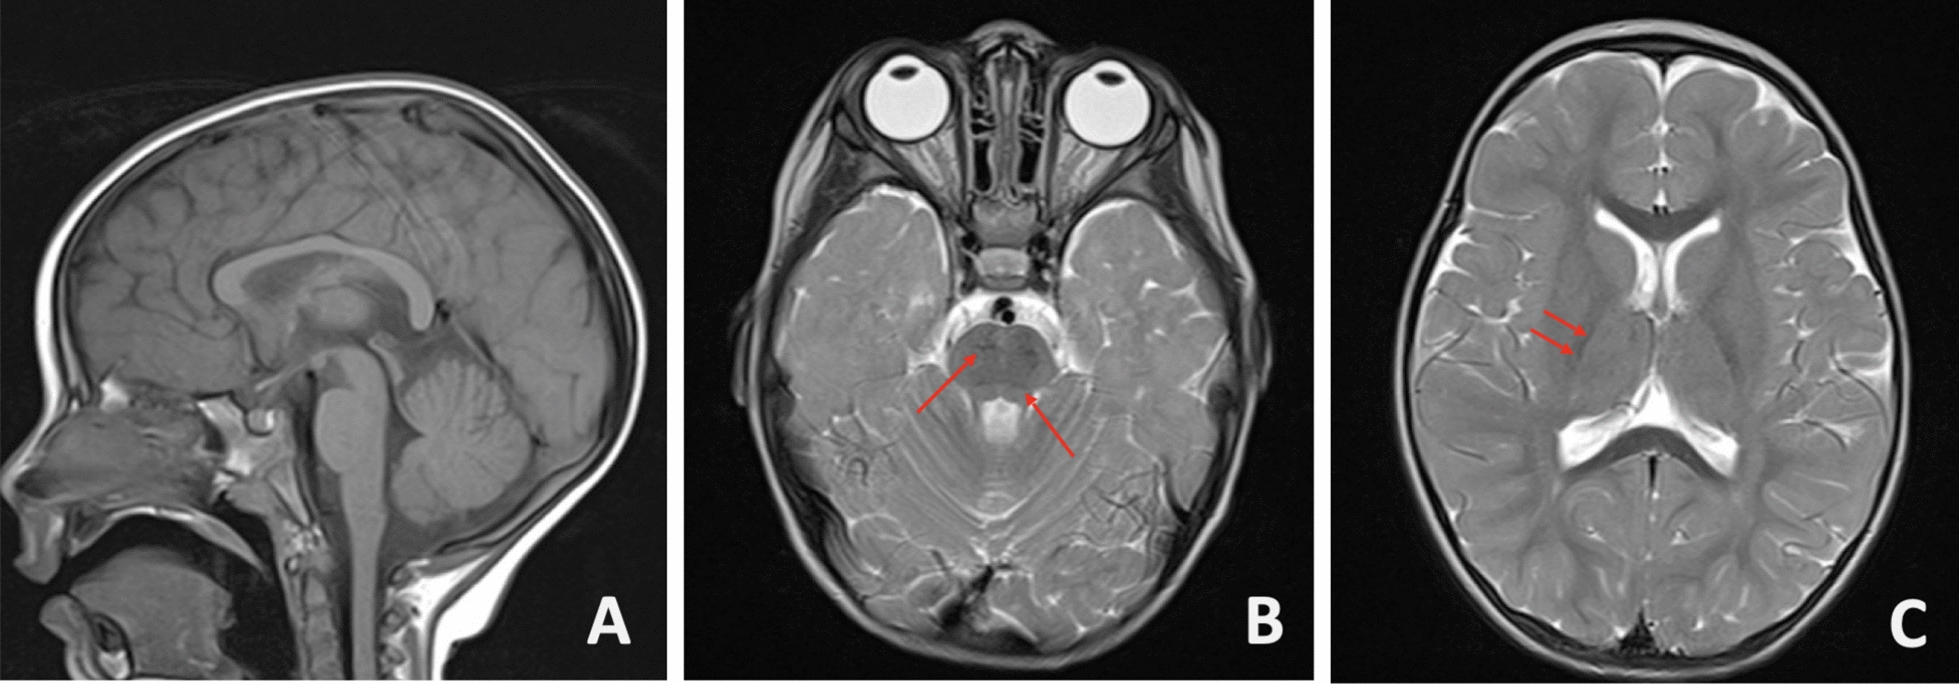

Case presentation: This study presents the case of a 3-year-old Uruguayan girl with suspected autosomal recessive spastic ataxia of Charlevoix-Saguenay, demonstrating the disease's presence in previously unreported locations. Exome sequencing analysis revealed two compound heterozygous variants in the sacsin molecular chaperone gene, one of which was novel.